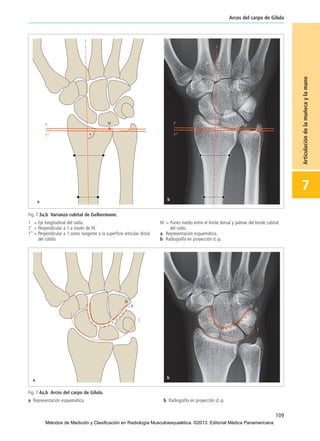

Fig. 7.3a,b Varianza cubital de Gelbermann.

1 = Eje longitudinal del radio.

1’ = Perpendicular a 1 a través de M.

1’’ = Perpendicular a 1 como tangente a la superficie articular distal

del cúbito.

M = Punto medio entre el límite dorsal y palmar del borde cubital

del radio.

a Representación esquemática.

b Radiografía en proyección d.-p.

Fig. 7.4a,b Arcos del carpo de Gilula.

a Representación esquemática. b Radiografía en proyección d.-p.

Arcos del carpo de Gilula

En una disposición regular de los huesos del carpo se pueden

delimitar en una radiografía en proyección d.-p. tres arcos ar-

mónicos, paralelos a lo largo de fila proximal (o primera fila) y

distal (o segunda fila) del carpo (Fig. 7.4). El 1er arco cursa a

lo largo del contorno proximal de la primera fila de los huesos

del carpo, el 2° en el contorno distal de la primera fila y el 3er

arco a lo largo del contorno distal de la segunda fila.

Toda interrupción del contorno de alguno de los arcos

debe considerarse como un signo indicador de una

inestabilidad carpiana.